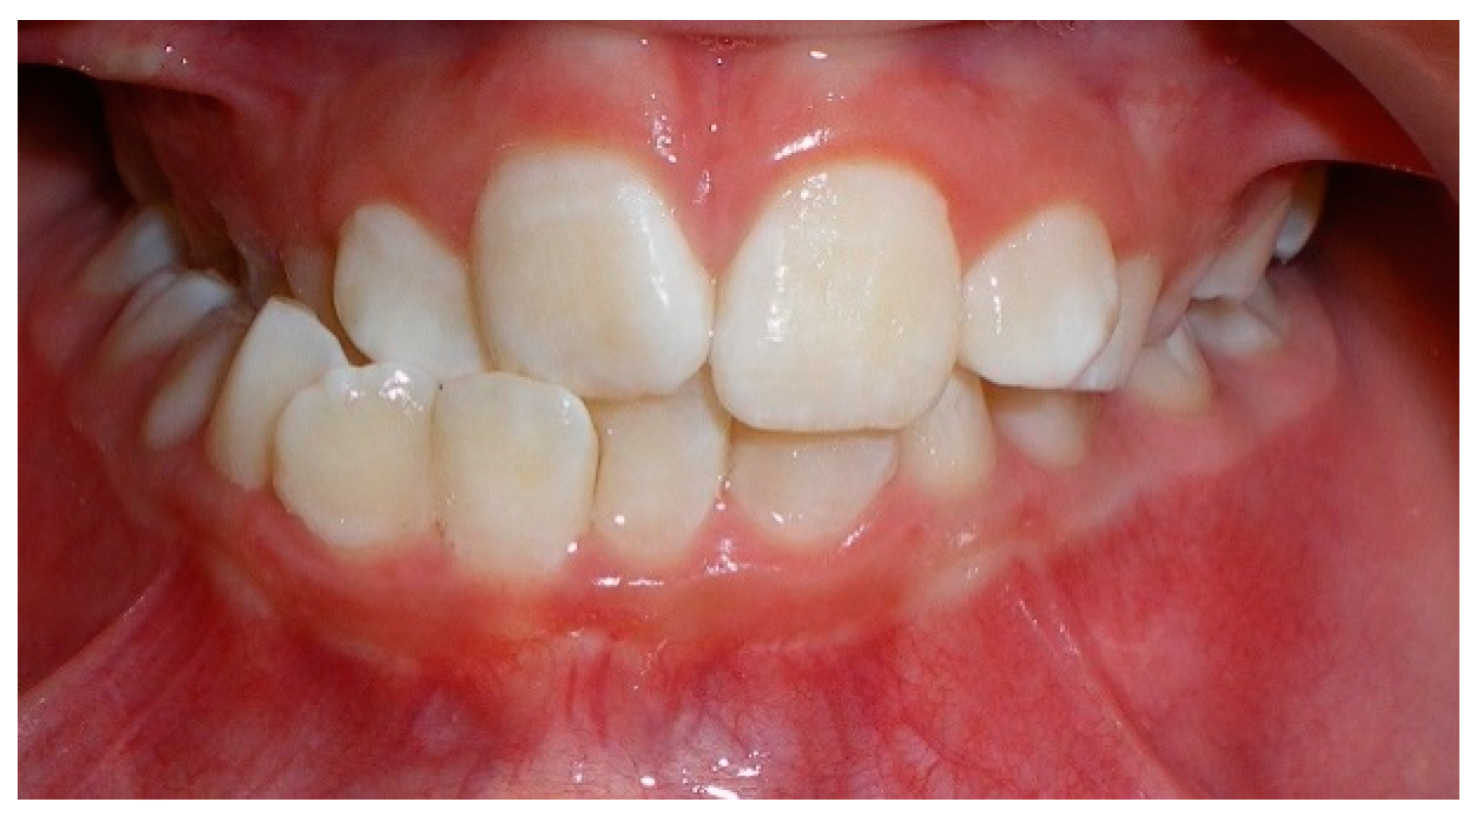

- Evaluation of impacted teeth, a common indication of CBCT in orthodontics. The advantages of CBCT include assessment of the tooth location and position, the stage of development, and status of adjacent teeth. CBCT is justified in these cases, because CBCT has the capability of evaluating the impacted teeth and adjacent structures more accurately than 2D conventional imaging. The benefit–risk ratio is favorable, especially if the CBCT volume is collimated to the impacted tooth. Figure 1, Figure 2, Figure 3 and Figure 4 show an example of impacted maxillary canines, and their proximity to the maxillary lateral incisors. Figure 1 shows an intraoral photograph. The benefit of CBCT acquisition in this case includes the ability to visualize the canines and the lateral incisors in three dimensions, which can be visualized in Figure 2 and Figure 3. In this case, the maxillary right lateral incisor exhibited external root resorption, a finding that would be difficult to see on a conventional 2D panoramic radiograph. Figure 4 shows a Maximum Intensity Projection of a panoramic view derived from the CBCT volume. This unique view is free of magnification, distortion, ghost images, and overlaps frequently seen in conventional 2D panoramic radiography.